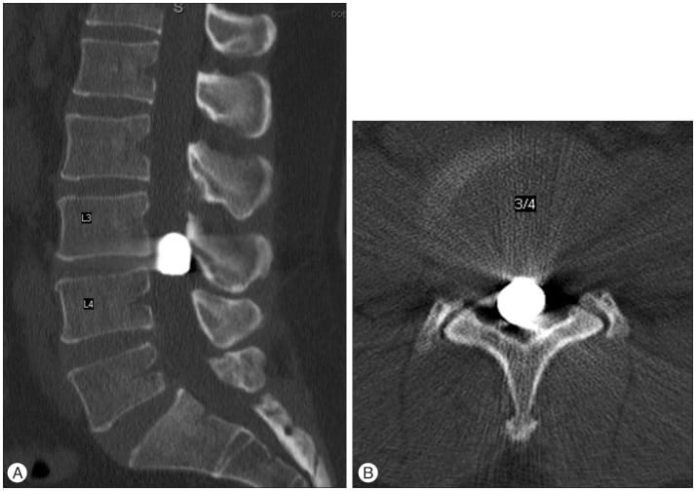

He was transported to the JNF Hospital via the ambulance. An x-ray has revealed that he received a single gunshot wound and the bullet is lodged behind his spine.